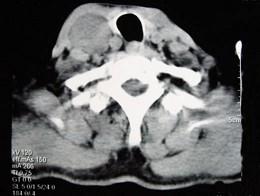

问题 男性,70岁,右侧颈部无痛性肿块3个月,CT扫描如图所示,请选择正确的描述和答案 ( )

选项 A、考虑迷走神经源性肿瘤 B、考虑交感神经源性肿瘤 C、右侧颈静脉被推压至肿块外后方 D、右侧颈动脉被推压至肿块内后方 E、右颈动脉间隙内见类圆形软组织肿块影,密度欠均匀,边缘光整

答案 ACDE